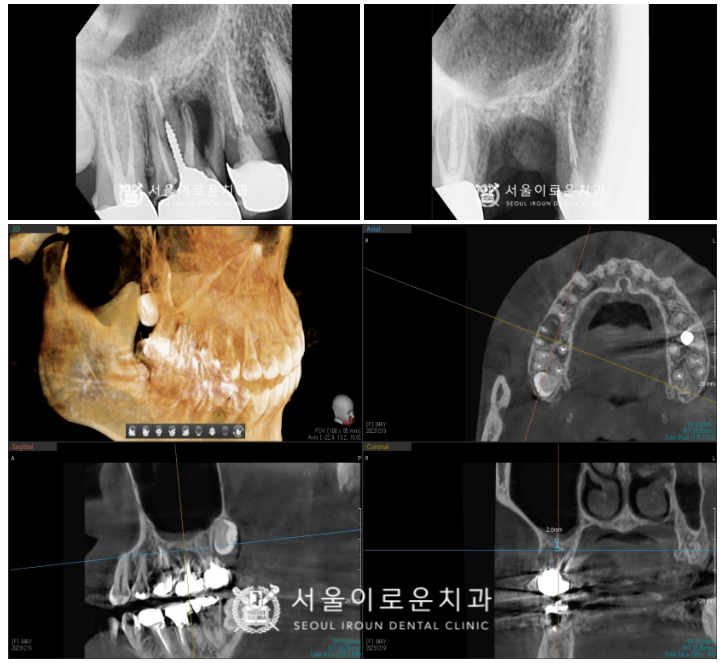

더불어 오른쪽 임플란트 수술 후

픽스쳐가 잇몸뼈에

단단히 고정되기를 기다리는 동안

왼쪽 아래턱 치아 치료를 진행하였는데요.

송곳니(#33) 충치 제거 후 레진을

첫 번째 작은 어금니(#34)는

신경치료 후 크라운까지

깔끔하게 마무리해 드렸답니다.

서울이로운치과에서

모든 치료가 마무리 된 후

촬영한 파노라마 사진입니다.

임플란트 / 레진치료 /

신경치료 / 크라운치료를

모두 깔끔하게 잘 도와드렸답니다.

✅ 전 > 후 ✅

(2024.01.06ㅡ>2024.06.07)